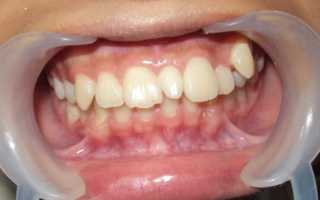

Сверхкомплектные зубы у детей появляются в постоянном прикусе и именно на передней группе — вместо 4 резцов верхней или нижней челюсти может появляться 5 и более. Обычно появление таких зубов становится причиной смещения соседних, правильно расположенных зубов. В остальном дети не предъявляют никаких жалоб.

Всем известно, что в ротовой полости должно находиться 32 зуба, это считается нормой. К аномалии количества зубов относится их избыточное количество, а также недостаток или полное отсутствие. Первая проблема имеет название – гипердонтия, и для нее характерно наличие сверхкомплектных зубов, которые находятся не в зубном ряду, а за его пределами и сильно смещают своих соседей в стороны, тем самым, меняя их нормальное положение на патологическое. Сверхкомплектные зубы чаще можно обнаружить на верхних рядах, их размеры и форма не совпадают с принятыми нормами. Довольно редко случается так, что сверхкомплектный зуб удачно втиснулся в зубной ряд.